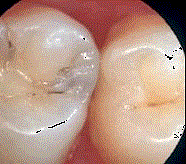

问题 龋好发于牙齿的 ( )

选项 A.自洁区 B.边缘嵴 C.滞留区 D.舌面 E.牙尖

答案 C